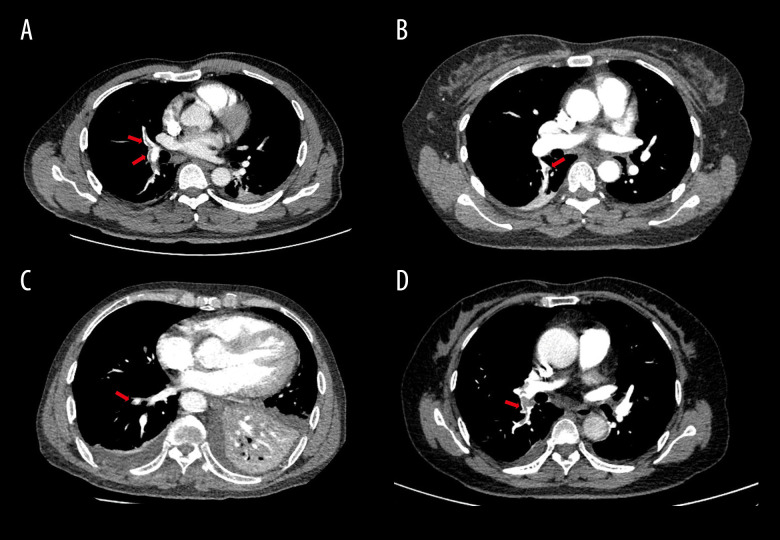

BACKGROUND Living donor liver transplantation (LDLT) is an established treatment for end-stage liver disease, where donor safety remains a top priority. Pulmonary embolism (PE) is an unpredictable but serious complication following liver donor hepatectomy (LDH), contributing significantly to postoperative morbidity and mortality. CASE REPORT This article reports 4 cases of PE in living donors following LDH, discussing their clinical presentations, diagnosis, and treatment, and reviewing the relevant literature. Patient 1 was a 46-year-old man who underwent laparotomy right hepatectomy and developed PE on postoperative day (POD) 2. Patient 2 was a 42-year-old woman who donated the left half liver for her son. On POD 8, she was diagnosed with PE by enhanced computed tomography (CT) scan. Patient 3 was a 65-year-old man with 2 years history of hypertension. He underwent a laparotomy right hepatectomy and developed PE on POD 2. Patient 4 was a 57-year-old woman who underwent laparotomy left hepatectomy with the middle hepatic vein. On POD 3, the patient suddenly developed dyspnea after ambulation, and the enhanced CT of pulmonary arteries showed extensive PE in both lungs. All donors developed symptoms such as dyspnea and hypoxemia postoperatively, and were diagnosed with PE through imaging studies. Prompt anticoagulation therapy led to favorable outcomes in all cases. CONCLUSIONS Although PE is a rare and serious complication after LDH, early recognition and timely intervention are crucial to prevent catastrophic outcomes for the donor. Improving perioperative management is key to enhancing donor safety.